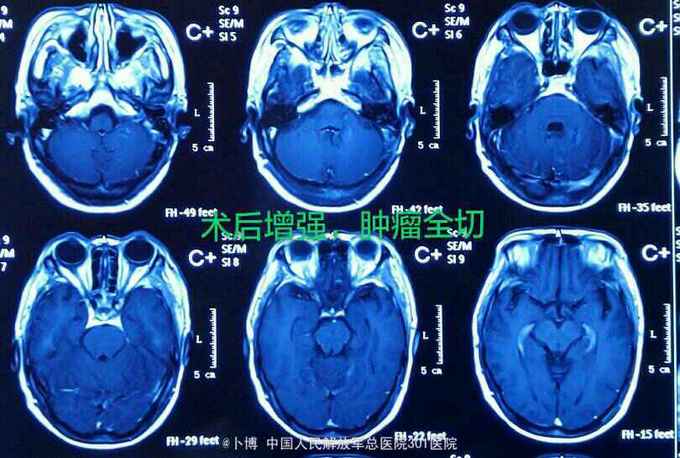

诊断:左侧岩斜脑膜瘤。 手术:乙状窦后入路。肿瘤位于面听神经的前方,将三叉神经根推向内侧。为了扩大显露并彻底切除肿瘤(基底),磨除了部分道上结节的骨质。 肿瘤全切。面听神经及三叉神经保留。

术后三个月复查。肿瘤全切。患者有面部麻木,疼痛消失。有轻度面瘫。听力尚存。